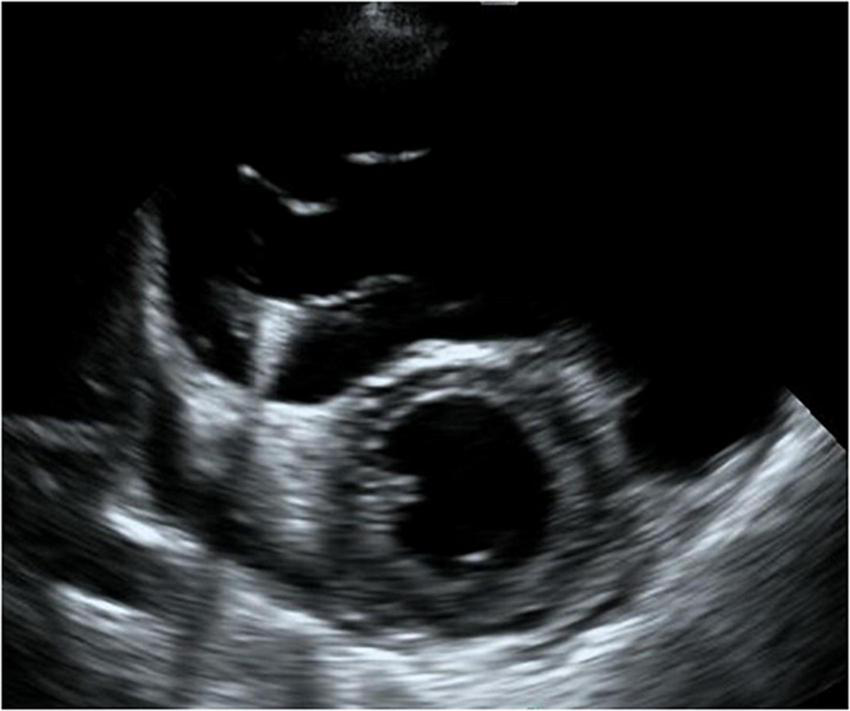

FIGURE 2

Four-chamber view at end-systolic phase of transthoracic echocardiography in Case 1. Note that the tricuspid valve does not close at all, and the right atrium is hugely dilated.